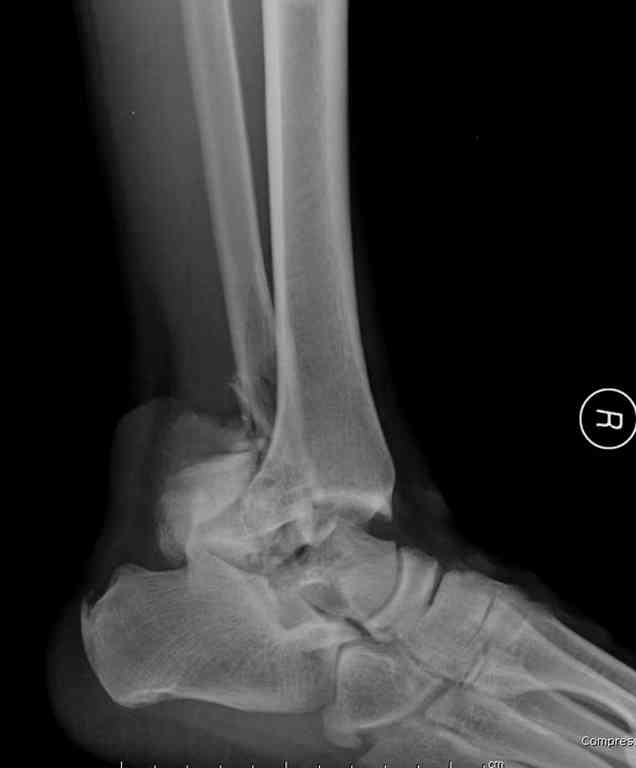

Прошу коллег помочь советом.3 дня назад поступила пациентка 23 года с переломом шейки ладьевидной справа, переломом лодыжек и заднего края б/берцовой кости со смещением и подвывихом кзади, переломом внутреннего мыщелка правого бедра без смещения. Дежурными хирургами проведена репозиция в левом г/ст суставе успешная, попытка репозиции таранной кости ухудшило положение отломков. Планируем провести повторную репозицию и фиксацию винтами. 1. Закрытая репозиция рентгенконтоль интраоперационный (аппарат Арман) ификсация из заднее-наружного доступа. 2. При неудачной закрытой репозиции переходим на открытое вправление двумя доступами медиальным и латеральным "по ходу оси таранной кости" и через дополнительный задний доступ вводим винты кортикальные 4,5 мм или 3,5 мм 3. после открытой репозиции фиксация двумя винтами через боковые доступы погружая их под суставную поверхность Сергей Зырянов ЦРБ Новосибирская область

Переломовывих тарана с повреждением медиальной стороны. Через 4 часа после поступления проведена репозиция и фиксация тарана после Irrigation&Debridment. Частичное несращение медиальной лодыжки не беспокоит, вернулся к активному образу жизни. Полная нагрузка разрешена через 11 недель. Финальные снимки через 11 месяцев.